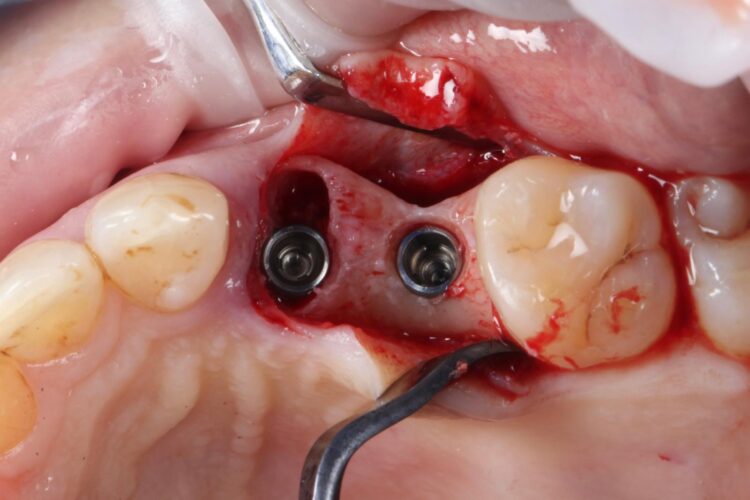

Two 3.8mm diameter CONELOG® Progressive-Line implants were placed through the guide, following the plan precisely. The UL4 implant was longer (11mm) to ensure sufficient apical bone was engaged for primary stability, it was also positioned in the palatal root to ensure good engagement with the bone and better bone to implant contact. A sizable jump gap was noted between the implant and the buccal plate of around 5-6mm. From a biological perspective, the jump gap can be left because the ridge would heal to leave a sufficient buccal plate. However, the literature[iv] shows that grafting reduces the amount of bone resorption post implant placement, which was one of the reasons that augmentation was indicated in this case.

Another predetermined concern was the amount of remaining bone surrounding an implant after placement. There was less than 2mm of residual bone buccal to the UL5 site once the implant was placed. Alberto Monje et al. (2023) [v] showed that thin buccal bone at the implant site increases the risk of major dimensional changes, this can have direct implications on the aesthetics and functional outcomes.

Consequently, the bone was contour-augmented, using MinerOss® Blend (BioHorizons Camlog), which provides a good combination of cortical and cancellous bone for efficient bone turnover and also maintains graft stability in the healing phase. The graft was held in place with a collagen membrane stabilised using resorbable sutures. The custom healing abutment is then placed and torqued (10Ncm) into the UL4 implant before the wound is approximated and sutured using a non-resorbable 6-0 Prolene suture.